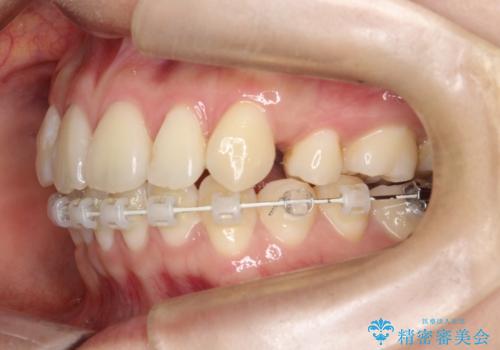

- 出っ歯、ガタツキ、噛み合わせが気になるとのことで来院された患者様です。

小臼歯を抜歯することでスペースを作り、前歯を下げて口元を下げ、Eラインを改善する治療方針としました。

表側のワイヤーは見た目が気になるとのことで、上の歯だけ裏側に付くハーフリンガルという装置で治療を行いました。